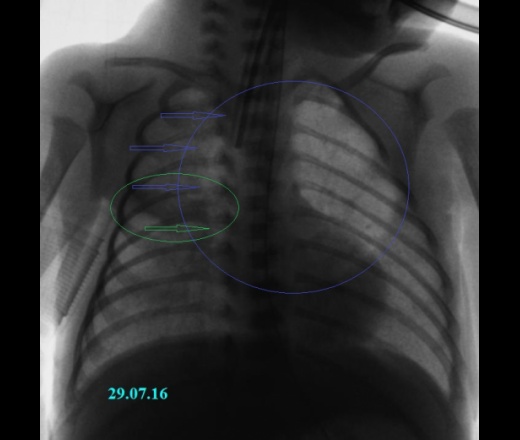

Рентгеновские снимки при врожденной эмфиземе легкого

Раздел: Визуальные уроки